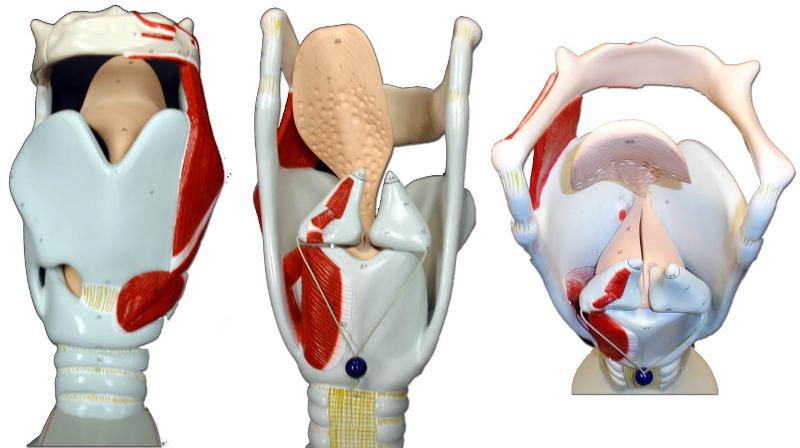

Larynx

Epiglottis

Vocal folds (=vocal cords)

C-Rings (=tracheal cartilage)

Trachae